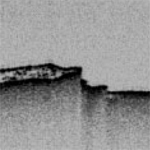

Imaging Pharmaceutical Tablets with Optical Coherence Tomography

J. M. A. Mauritz, et al., Journal of Pharmaceutical Sciences, 99 (1), 2009.

Link